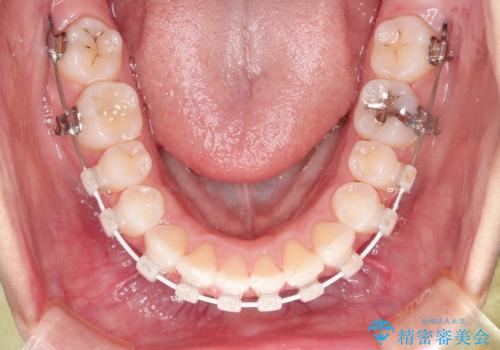

- 前歯のがたつきと出っ歯が気になるとのことで来院されました。

上顎の前から4番目の歯を両側合計2本抜歯して矯正することとなりました。

抜歯をして矯正をすることで、前歯を後方に移動させ、ガタガタを改善することができました。